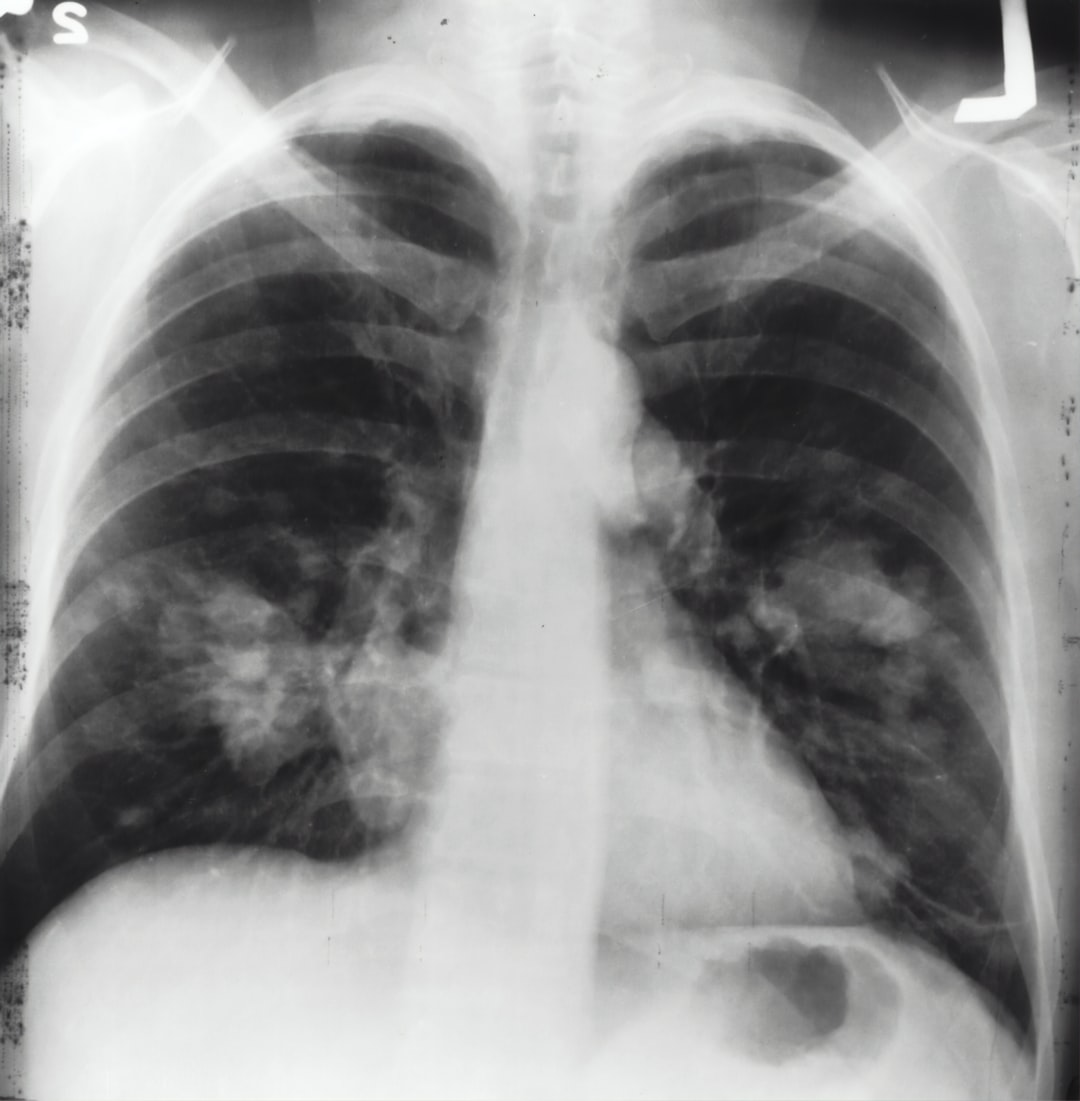

폐암은 전 세계적으로 가장 흔한 암 유형의 하나로, 그 심각성과 높은 발병률로 인해 많은 사람들에게 영향을 미치고 있습니다. 폐암은 폐에서 시작되는 악성 종양으로, 조기에 발견되지 않으면 치명적일 수 있습니다. 폐암은 흡연, 환경적인 요인, 유전적인 요소 등 다양한 원인에 의해 발생할 수 있으며, 주로 폐 조직에서 암세포의 비정상적인 성장과 전이가 일어납니다.

폐암은 초기 단계에서는 특별한 증상이 없을 수 있어 진단이 어려운 경우가 많습니다. 그러나 진행됨에 따라 기침, 호흡 곤란, 가슴 통증 등의 증상이 나타날 수 있으며, 이러한 증상은 환자와 주변 사람들에게 큰 고통을 안겨줍니다.

이 글에서는 폐암에 대한 이해를 높이고, 초기 증상부터 치료 방법에 이르기까지 다양한 측면을 다루어보고자 합니다. 폐암은 치료 가능성과 생존율이 발전하고 있으며, 조기 발견과 적절한 치료를 통해 예방하고 통제할 수 있는 암입니다.